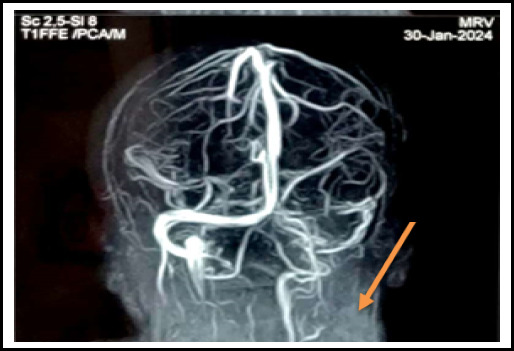

Pregnancy is the pro-thrombotic state. The objective of this report is to highlight the rare occurance of postpartum cavernous sinus thrombosis associated with eclampsia and gestational diabetes mellitus, emphasizing its clinical presentation. A 25-year-old Muslim female came with the complaint of headache,post auricular and right parietal region on 8th day post-partum. She had a history of postpartum eclampsia and Gestational Diabetes Mellitus for which she was treated with magnesium sulfate and oral hypoglycaemic agents respectively. MRV showed a filling defect in right transverse sinus, sigmoid sinus, and internal jugular vein. She was then admitted to the ward and was treated with heparin and antibiotics. She was then discharged on oral rivaroxaban. As pregnancy is itself a state of hyper-coagulable state, there seems to be a significant thrombosis risk. Hence clinicians should be aware of the possible thrombotic disorder in the background of this vignette.

妊娠是促血栓形成的状态。本报告的目的是强调产后海绵窦血栓形成合并子痫和妊娠糖尿病的罕见发生,并强调其临床表现。25岁穆斯林女性,产后第8天主诉头痛、耳后及右顶骨区。患者有产后子痫和妊娠期糖尿病病史,曾分别给予硫酸镁和口服降糖药治疗。MRV显示右横窦、乙状窦及颈内静脉充盈缺损。随后,她住进了病房,接受了肝素和抗生素治疗。她随后口服利伐沙班出院。由于妊娠本身就是一种高凝状态,因此似乎存在明显的血栓形成风险。因此,临床医生应该意识到在这个小插曲的背景下可能的血栓性疾病。